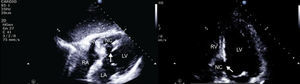

Although the patch significantly reduced the interventricular communication, a residual defect remained, with turbulent left-to-right shunt, draining into a cavity that corresponded to the aneurysmal dissection of the septum, and that communicated distally with the right ventricle (Figure 2), findings confirmed by cardiac magnetic resonance imaging (Figures 3 and 4).

Transthoracic echocardiography, subcostal view. After surgery, an interventricular communication remains, with left-to-right shunt. LA: left atrium; LV: left ventricle; NC: neocavity formed by the dissection of the interventricular septum; RA: right atrium. Arrow: interventricular septal rupture.